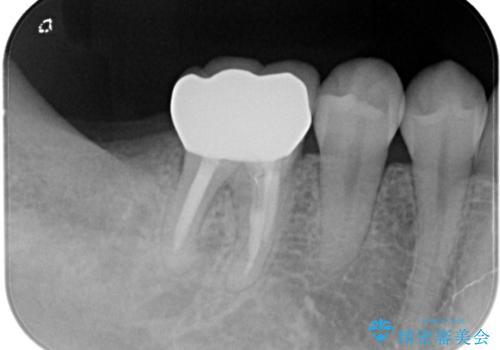

根管治療を行なったのちオールセラミッククラウンにて修復補綴を行いました。

根管治療歯は破折を防止するために速やかに被せ物の治療を提案いたします。